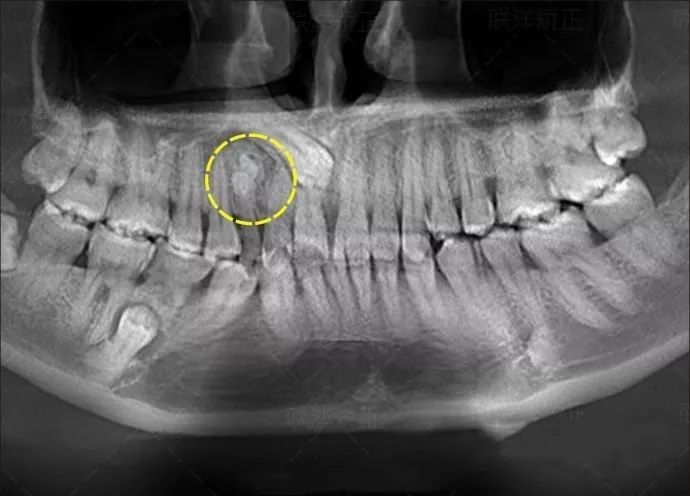

今日嘅朋友圈,唔少牙醫都喺轉發呢個一篇評論同相片——

試想,如果冇拍片,直接貿然拔牙,一旦出現問題......一張牙片,“救”咗病人,更救了診所!

再嚟睇一個案例——

牙齒嘅硬度比骨骼仲硬,僅憑肉眼檢查係睇唔到牙齒內部嘅情況嘅。

例如當牙齒有好深嘅齲壞時,憑口內檢查嚟話唔到齲洞有幾深、離牙神經有幾遠同埋有冇同牙根發炎相關嘅資訊。

線片x線片唔止可以明白牙齒本身嘅病變情況,還可以明白牙根下有冇囊腫、周圍骨頭有冇吸收以及牙槽骨入面有冇埋伏牙、多生牙等。依據X線片綜合分析,可以提高齒科醫生診斷治療牙齒嘅準確性同成功率。